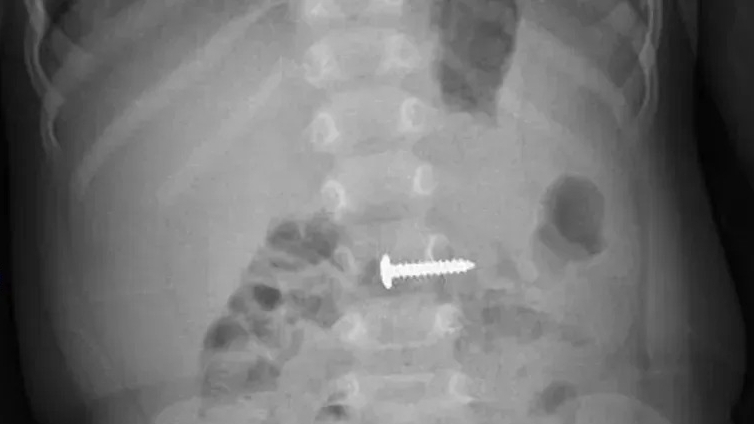

Bệnh nhân đã được tiến hành gây mê nội khí quản. Sau đó, các bác sĩ rạch một đường nhỏ dưới dương vật, cách bìu khoảng 2cm và đặt vào trong thể hang của người bệnh một thể hang nhân tạo giống như hai cái ống.

“Hai ống này có tác dụng làm dương vật cương lên giống thể hang thật. Qua đường mổ này, phẫu thuật viên tiếp tục đặt một túi chứa chất dịch (nước muối sinh lý đã được khử trùng) vào trước bàng quang, sau xương mu. Cuối cùng, đặt bơm vào giữa bìu. Ba hệ thống này sẽ nối với nhau qua hệ thống ống nối và toàn bộ hệ thống này nằm ẩn bên trong cơ thể, đảm bảo kín đáo và thuận tiện trong sinh hoạt”, PGS Quang thông tin.